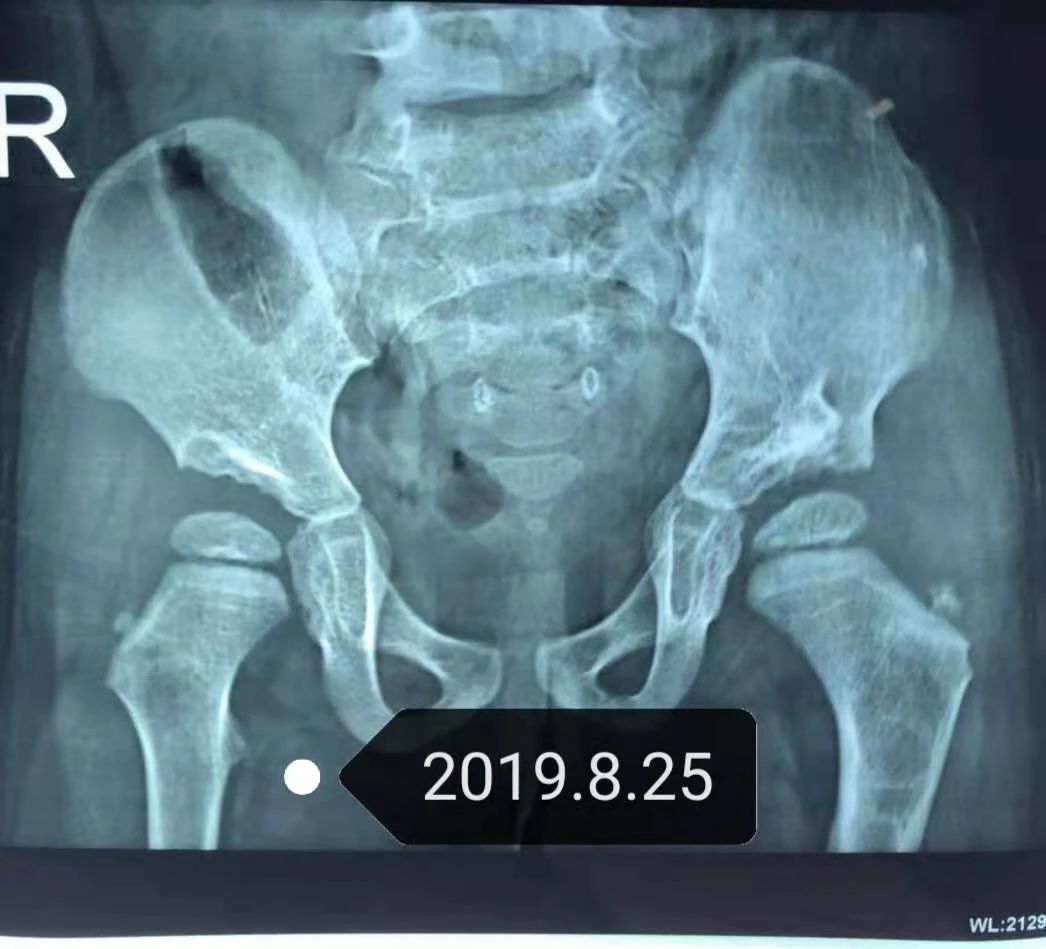

三年前,听到医生的诊断“先天性髋关节脱位”,突如其来的不幸让我沉浸于迟发现的自责中......

好不容易熬过了住院的时光,我回到家后发现宝贝走路还是容易摔倒,一检查髋关节依旧脱位,手术失败了,我再次陷入崩溃……

孩子爸爸终于还是没拗得住我,从甘肃到合肥,将近两千公里的路程,我们一家三口坐了二十多个小时火车风尘仆仆的赶来了。我们去的是小儿先髋动态稳定支具系统发明人胡大勇院长告知的合肥东南骨科医院,恰巧赶上他刚刚结束一台手术,只见他还没来得及摘下帽子和脱下手术服,就接待了我们,看了孩子的片子,分析了病情,讲解完治疗方案,见我丈夫半信半疑,就建议他去四楼看一下正在矫正中的其他宝宝。

当我们一家三口走入小儿骨科病区,孩子爸爸心终于“尘埃落定”。这里住着来自全国各地的先髋孩子,我的孩子此时已经2岁半了,来院后通过动态稳定系统治疗了为期45天,然后回家戴贝氏支具五个月。

去年五月,我独自一人带着快三岁多的她来做康复巩固,医院的医生和护士都夸她长大了不少,出落的亭亭玉立,而且通过拍片,胡院长告诉我,女儿基本恢复了,步态也趋于正常,我喜极而泣,欣慰极了。